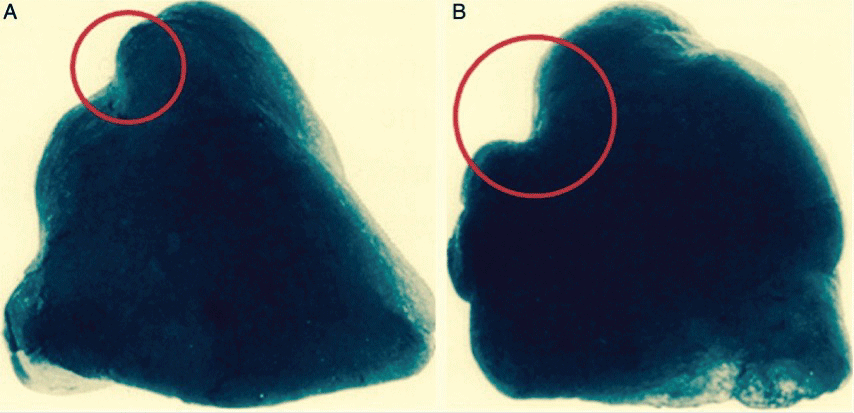

The lungs occupy the pleural cavity. This cavity is not smooth internally but characterized by ridges caused by the ribs. The most prominent rib ridge is that of the first rib. This may be such a deep furrow that a surgeon might feel a sharp edge on intra-operative palpation [21]; (Figure1). Computerized tomography scans in coronal and sagittal views show that the apex of the lung sticks out like a thumb from the rest of the lung; (Figure 2). The result is that the apex geometrically has the shape similar to that of a rugby ball or bullet, that is a prolate or elongated spheroidal shape.

Figure 1: A,B) Anterior and posterior views of moulds of the lung apex showing prominent indentations in the lung parenchyma caused by rib furrows, especially that of the first rib which are deeper posteriorly. Modified after Stephenson [21]. View Figure 1